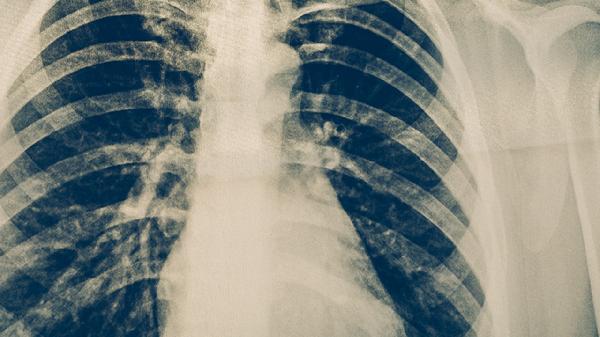

隱性結(jié)核感染并非絕對無害,部分患者可能在影像學(xué)檢查中發(fā)現(xiàn)肺部陳舊性病灶或鈣化點,提示既往感染。結(jié)核菌素皮膚試驗或γ-干擾素釋放試驗陽性是診斷隱性感染的主要依據(jù)。對于高風(fēng)險人群,如與活動性結(jié)核患者密切接觸者、醫(yī)務(wù)工作者等,即使無癥狀也建議進行篩查。預(yù)防性治療可選用異煙肼片、利福平膠囊等藥物,但需嚴(yán)格評估肝腎功能并在醫(yī)生指導(dǎo)下用藥。

定期體檢有助于早期發(fā)現(xiàn)隱性結(jié)核感染,特別是胸部X線或CT檢查能識別輕微病變。保持充足睡眠、均衡飲食、適度運動有助于維持免疫力,降低隱性感染轉(zhuǎn)為活動性的概率。若家庭成員確診結(jié)核病,其他成員應(yīng)接受篩查,隱性感染者需遵醫(yī)囑決定是否進行預(yù)防性治療。出現(xiàn)持續(xù)兩周以上的乏力、食欲下降等非特異性癥狀時,應(yīng)及時就醫(yī)排除結(jié)核病可能。